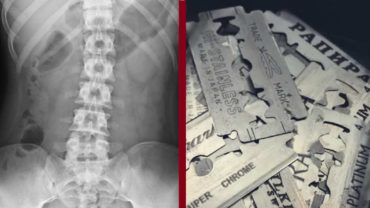

অস্ত্রোপচারে যুবকের পেট থেকে বের হলো ৫৬ টুকরা ব্লেড!

আন্তর্জাতিক